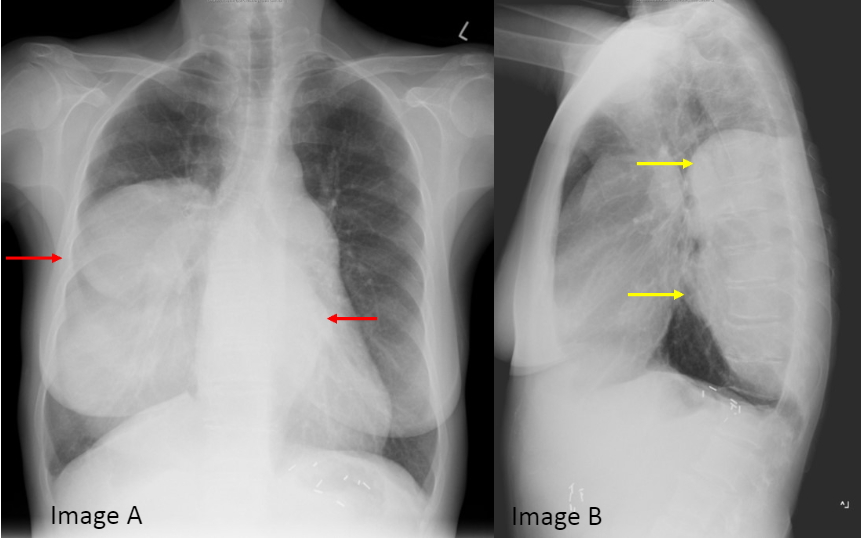

Axial CT in this patient with a history of splenectomy, shows bilateral paraspinal masses with soft tissue attenuation (image C, orange arrows) that have hypoattenuation, likely representing central fatty change (image C, green arrow). Findings are consistent with extramedullary hematopoiesis.

患者有脾切除史,横轴位CT显示双侧椎旁软组织密度肿块(图C,橙色箭头),其内可见散在低密度区,可能提示肿块中心脂肪变(图C,绿色箭头)。 影像表现符合髓外造血。